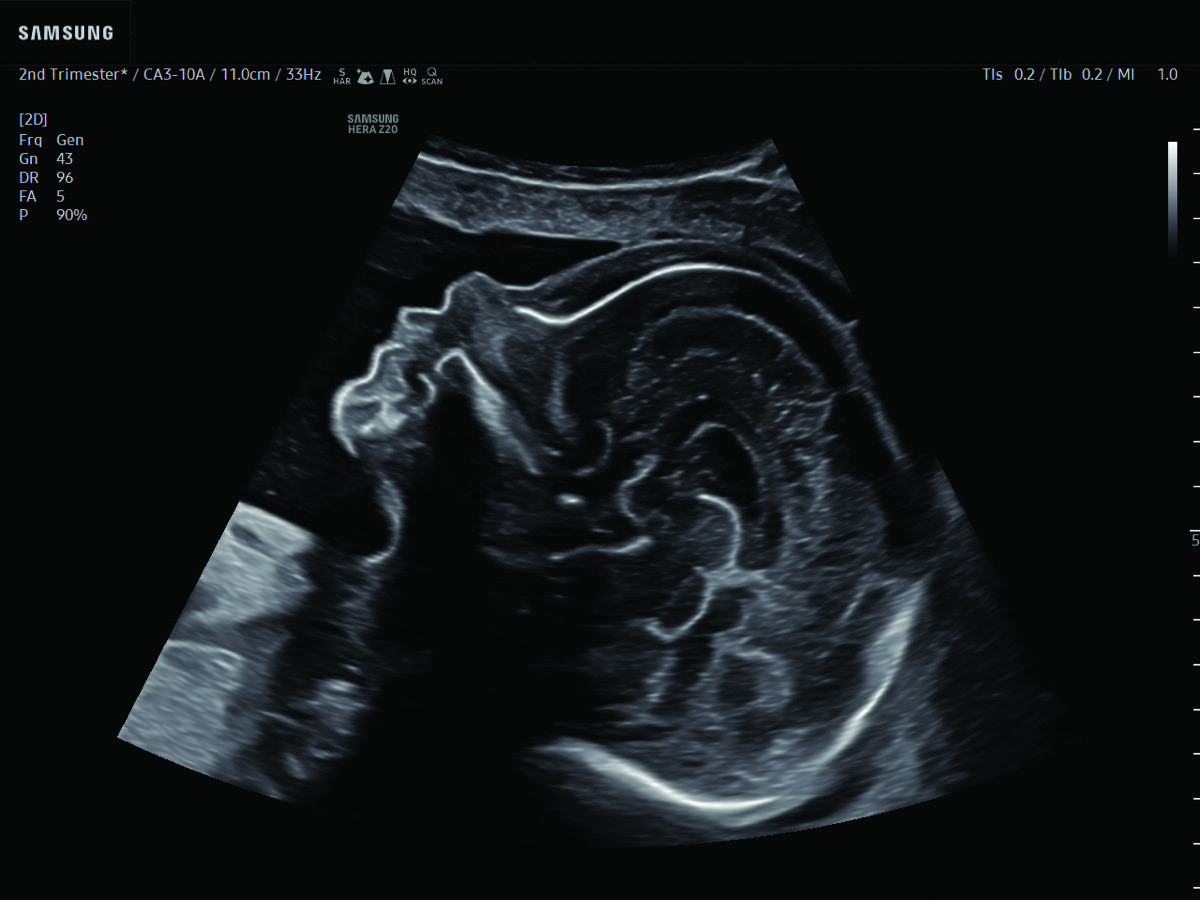

Comprehensive, advanced and expert MFM care for high-risk pregnancies

- Fetal anomalies